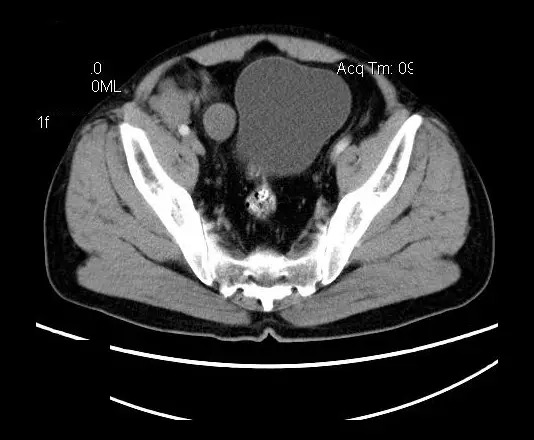

【影像表现】

盆腔右前侧及邻近腹股沟区可见多发大小不等的聚集生长的结节影,病灶呈软组织密度,边缘尚规整,分界尚清,增强扫描可见不均匀强化。膀胱局部受压,盆腔未见明显肿大淋巴结影。

平扫影像表现:Antoni A区较多病灶,在CT上呈等或略高密度影,T1WI等信号、T2WI略高信号,AntoniB区较多病灶,CT多为水样低密度、T1WI低信号、T2WI明显高信号。

增强影像表现:神经鞘膜肿瘤增强后,由于Antoni A区与B区以不同比例混合而强化不一,呈不均匀斑片状,条状强化。Antoni A 区富血供,中等或明显强化,Antoni B区乏血供,强化多不明显。